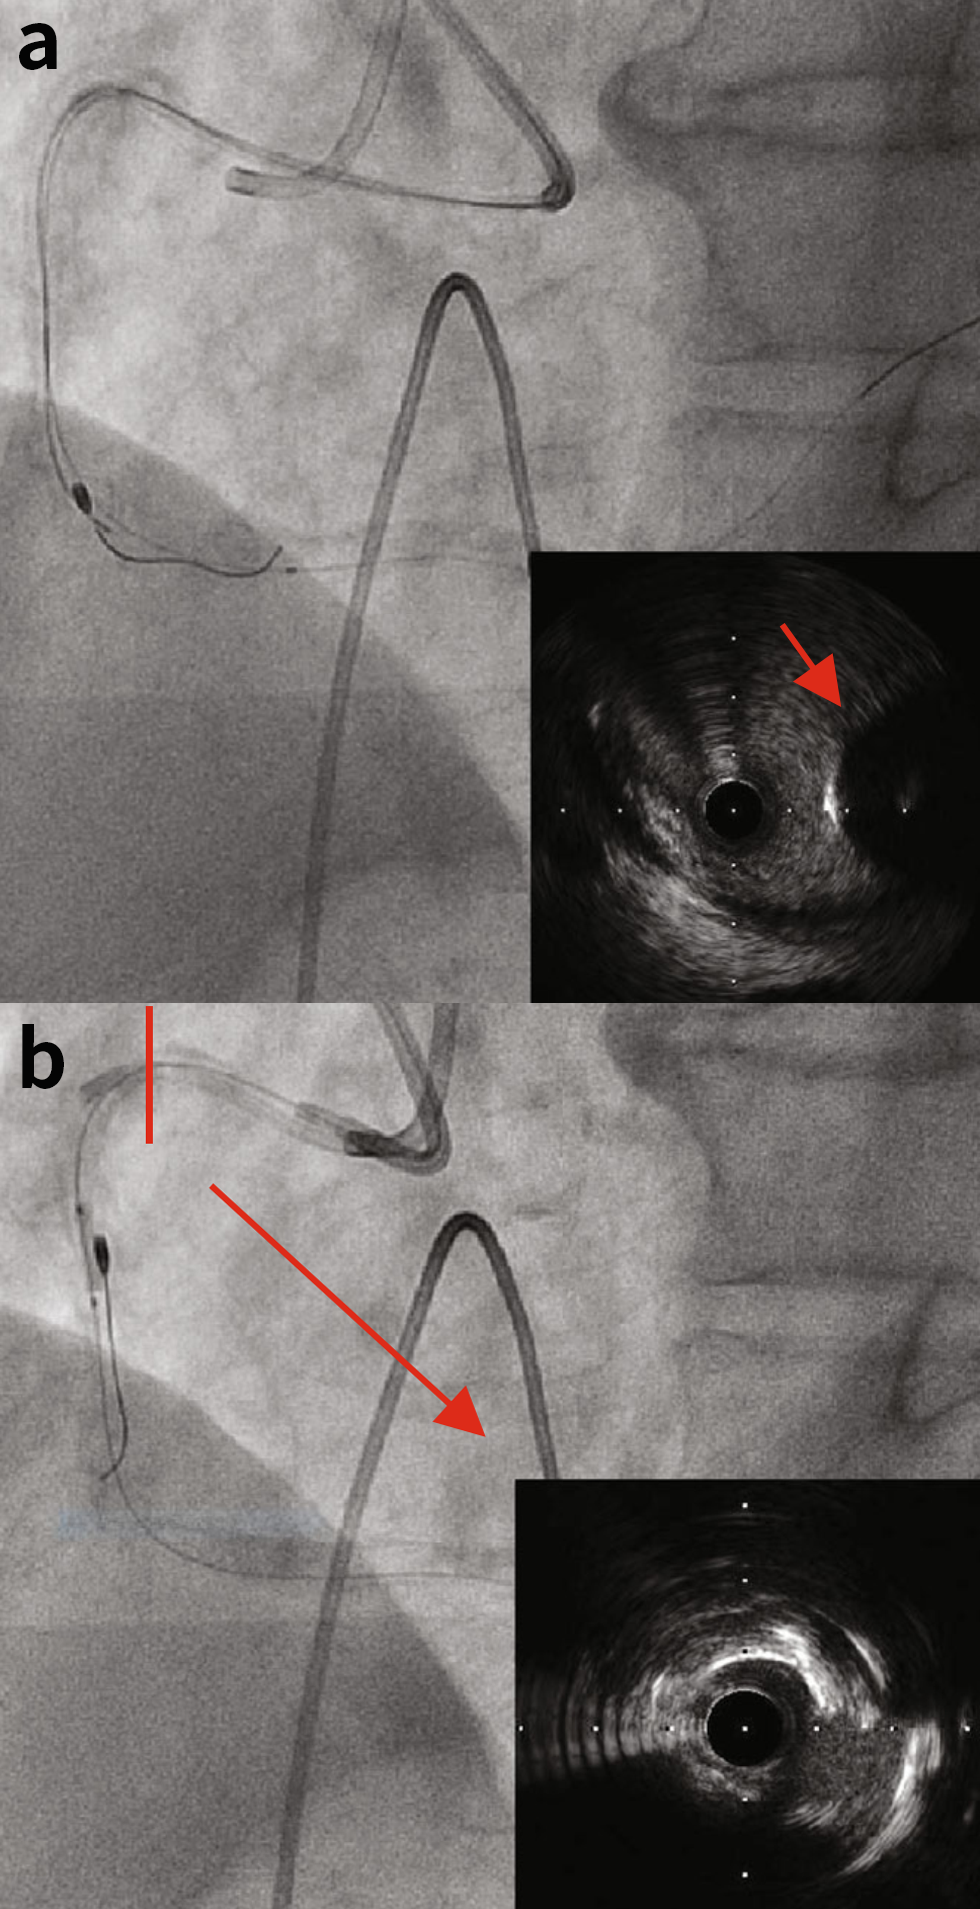

由于IVUS和小直径球囊无法通过(视频1),因此使用微导管将SION blue导丝替换为旋磨导丝。以180,000转/分的转速并采用缓慢的前后“啄米式”运动(每次运行最多20秒),通过消蚀RCA近端部分,将1.5mm磨头推进。将转速保持在175,000转/分以上。随后,对中段重度狭窄病变进行消蚀。然而,我们观察到,尽管驱动轴被来回拉动,但当旋磨头推进到远端RCA时,旋磨头从驱动轴上脱落(图1(b)和图2(b),视频2和视频3)。幸运的是,冠脉前向血流得以保持,且旋磨导丝没有断裂。

图1.(a)基线冠状动脉造影。(b)驱动轴与磨头分离(红色箭头表示驱动轴的边缘)。

图2. (a)最终冠状动脉造影。(b)断开的旋磨头和驱动轴的边缘(红色箭头)。(c)旋磨导丝的远端和主体部分。

第二根导丝从第二根导丝(7-Fr JR4.0)推进到远端RCA,并使用IVUS观察旋磨头。值得注意的是,旋磨头没有被困在这个地点(图3(a))。然后将旋磨导丝软头用作锚点,将旋磨头拉向近端RCA,这得益于旋磨导丝尖端的0.014英寸直径。然而,旋磨头被困在RCA中期狭窄的钙化中。

将另一根导丝从第二根指引导管中推送至RCA远端,并使用IVUS观察磨头。旋磨头并没有被困住(图3(a))。随后,使用旋磨导丝头端作为类似于绳结的锚点,将向RCA近端拉拽,这得益于旋磨导丝头端的0.014英寸直径(译者注:旋磨导丝头端直径0.014英寸,体部0.009英寸)。然而,旋磨头被卡在RCA中段狭窄的钙化部位内。

图3.(a)使用IVUS观察旋磨头。旋磨头没有被困住。(b)在被卡住的磨头旁边以2.5mm球囊扩张。IVUS观察到RCA近端病变的内侧被消蚀。